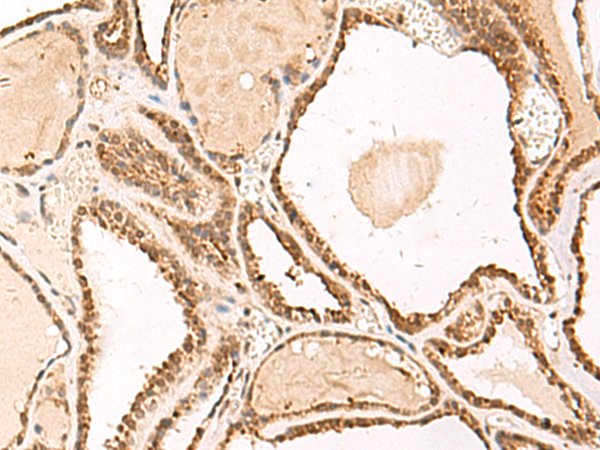

分类: 科研抗体货号: P10036别名: Efm4; METTL10; C10orf138应用: IHC反应种属: Human, Mouse